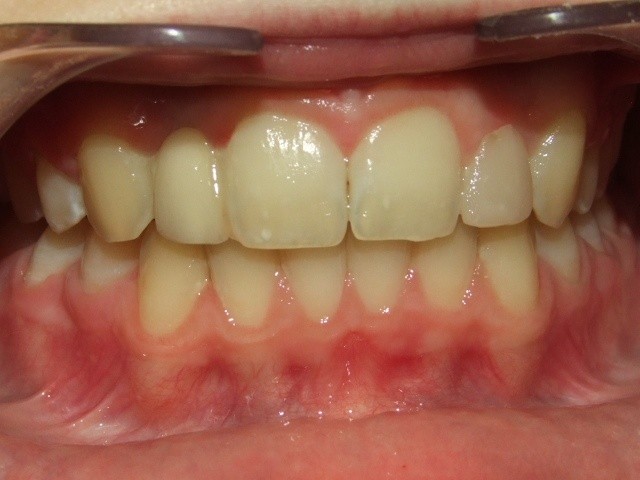

Na behandeling